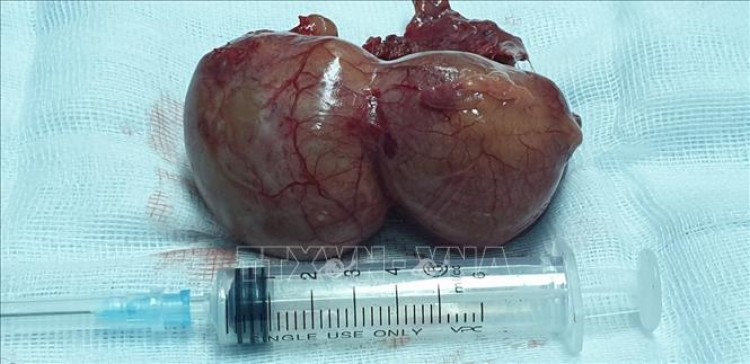

Nang màng ngoài tim đã được phẫu thuật cắt bỏ. Ảnh: TTXVN phát

Sau khi khám lâm sàng kết hợp chụp MSCT lồng ngực có tiêm thuốc cản quang, các bác sỹ phát hiện một khối nang màng ngoài tim kích thước lớn khoảng 40x70mm nằm cạnh động mạch chủ ngực, chèn ép vào tâm nhĩ phải. Bệnh nhân được chỉ định phẫu thuật.

Quá trình phẫu thuật, các bác sỹ đã kẹp và khâu cột cuống nang, lấy trọn khối nang ra ngoài, đặt ống dẫn lưu màng phổi phải và dẫn lưu màng tim. Sau 90 phút, ca phẫu thuật đã thành công. Hiện bệnh nhân đã rút nội khí quản, tỉnh táo, tiếp xúc tốt, hết khó thở và tiếp tục được theo dõi điều trị tại khu hậu phẫu mổ tim.